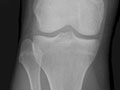

• Encontrar cambios en los huesos causados por afecciones, tales como infección, artritis, crecimientos óseos (tumores) u otras enfermedades de los huesos. Vea imágenes de osteoartritis de la cadera y de osteoartritis de la rodilla.